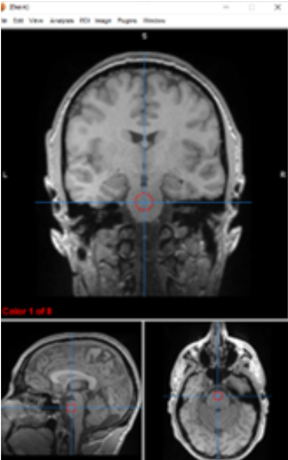

lateral ventricles

circulate and produce cerebrospinal fluid